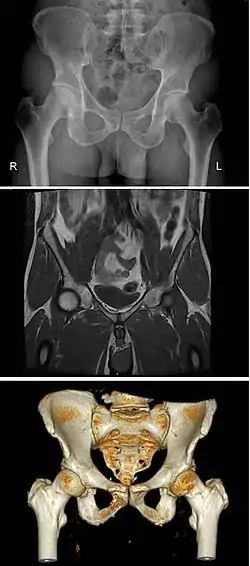

The pelvis (plural pelves or pelvises) is the lower part of the trunk,[1] between the abdomen and the thighs (sometimes also called pelvic region), together with its embedded skeleton[2] (sometimes also called bony pelvis, or pelvic skeleton).

The pelvic region of the trunk includes the bony pelvis, the pelvic cavity (the space enclosed by the bony pelvis), the pelvic floor, below the pelvic cavity, and the perineum, below the pelvic floor.[1] The pelvic skeleton is formed in the area of the back, by the sacrum and the coccyx and anteriorly and to the left and right sides, by a pair of hip bones.

The two hip bones connect the spine with the lower limbs. They are attached to the sacrum posteriorly, connected to each other anteriorly, and joined with the two femurs at the hip joints. The gap enclosed by the bony pelvis, called the pelvic cavity, is the section of the body underneath the abdomen and mainly consists of the reproductive organs (sex organs) and the rectum, while the pelvic floor at the base of the cavity assists in supporting the organs of the abdomen.

The pelvic region of the trunk is the lower part of the trunk, between the abdomen and the thighs.[1] It includes several structures: the bony pelvis, the pelvic cavity, the pelvic floor, and the perineum. The bony pelvis (pelvic skeleton) is the part of the skeleton embedded in the pelvic region of the trunk. It is subdivided into the pelvic girdle and the pelvic spine. The pelvic girdle is composed of the appendicular hip bones (ilium, ischium, and pubis) oriented in a ring, and connects the pelvic region of the spine to the lower limbs. The pelvic spine consists of the sacrum and coccyx.[1]

The pelvic skeleton is formed posteriorly (in the area of the back), by the sacrum and the coccyx and laterally and anteriorly (forward and to the sides), by a pair of hip bones. Each hip bone consists of three sections: ilium, ischium, and pubis. During childhood, these sections are separate bones, joined by the triradiate cartilage. During puberty, they fuse together to form a single bone.